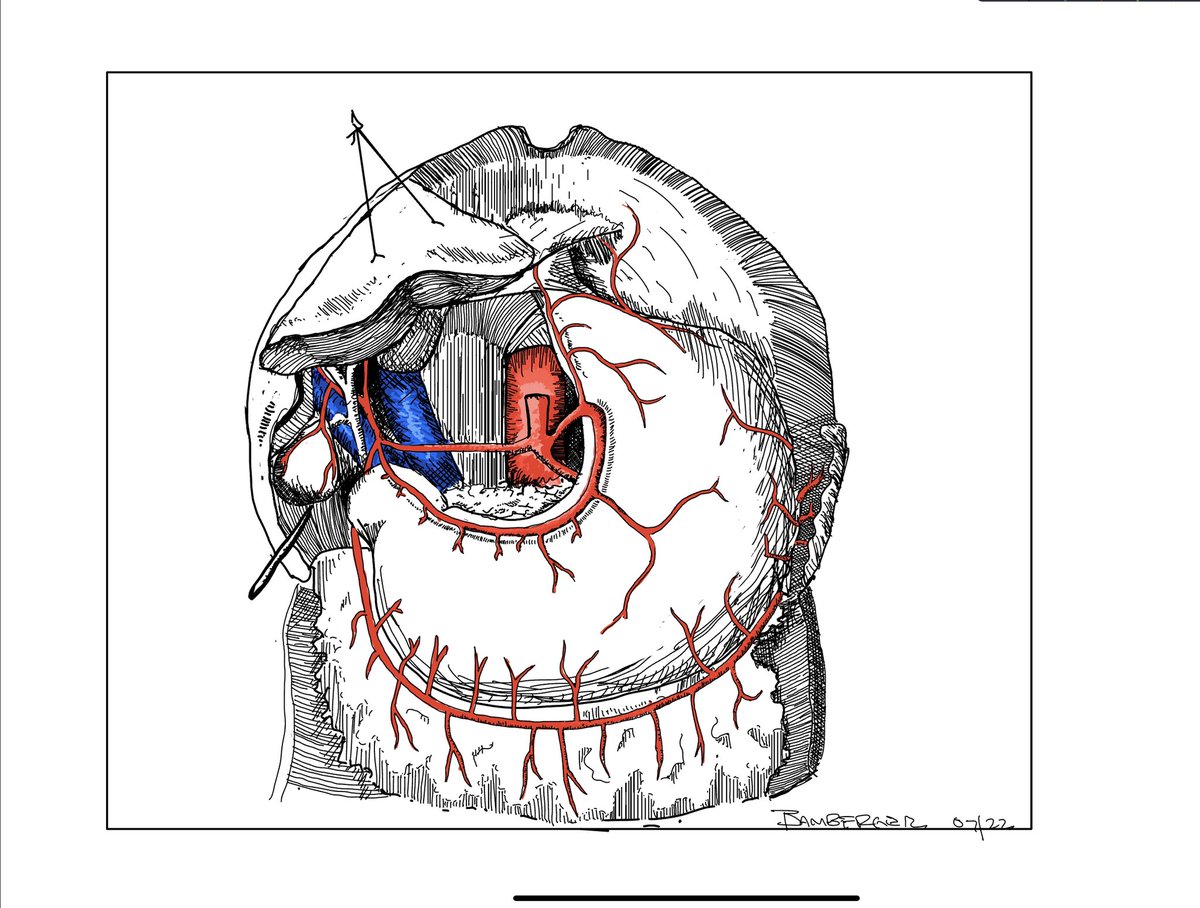

Can preop CT be used to predict impacted stones? Our model indicates HU under stone can predict impaction. Mantu Gupta, M.D. sciencedirect.com/science/articl…

Can preop CT be used to predict impacted stones? Our model indicates HU under stone can predict impaction. <a href="/MantuGuptaMD/">Mantu Gupta, M.D.</a> sciencedirect.com/science/articl…